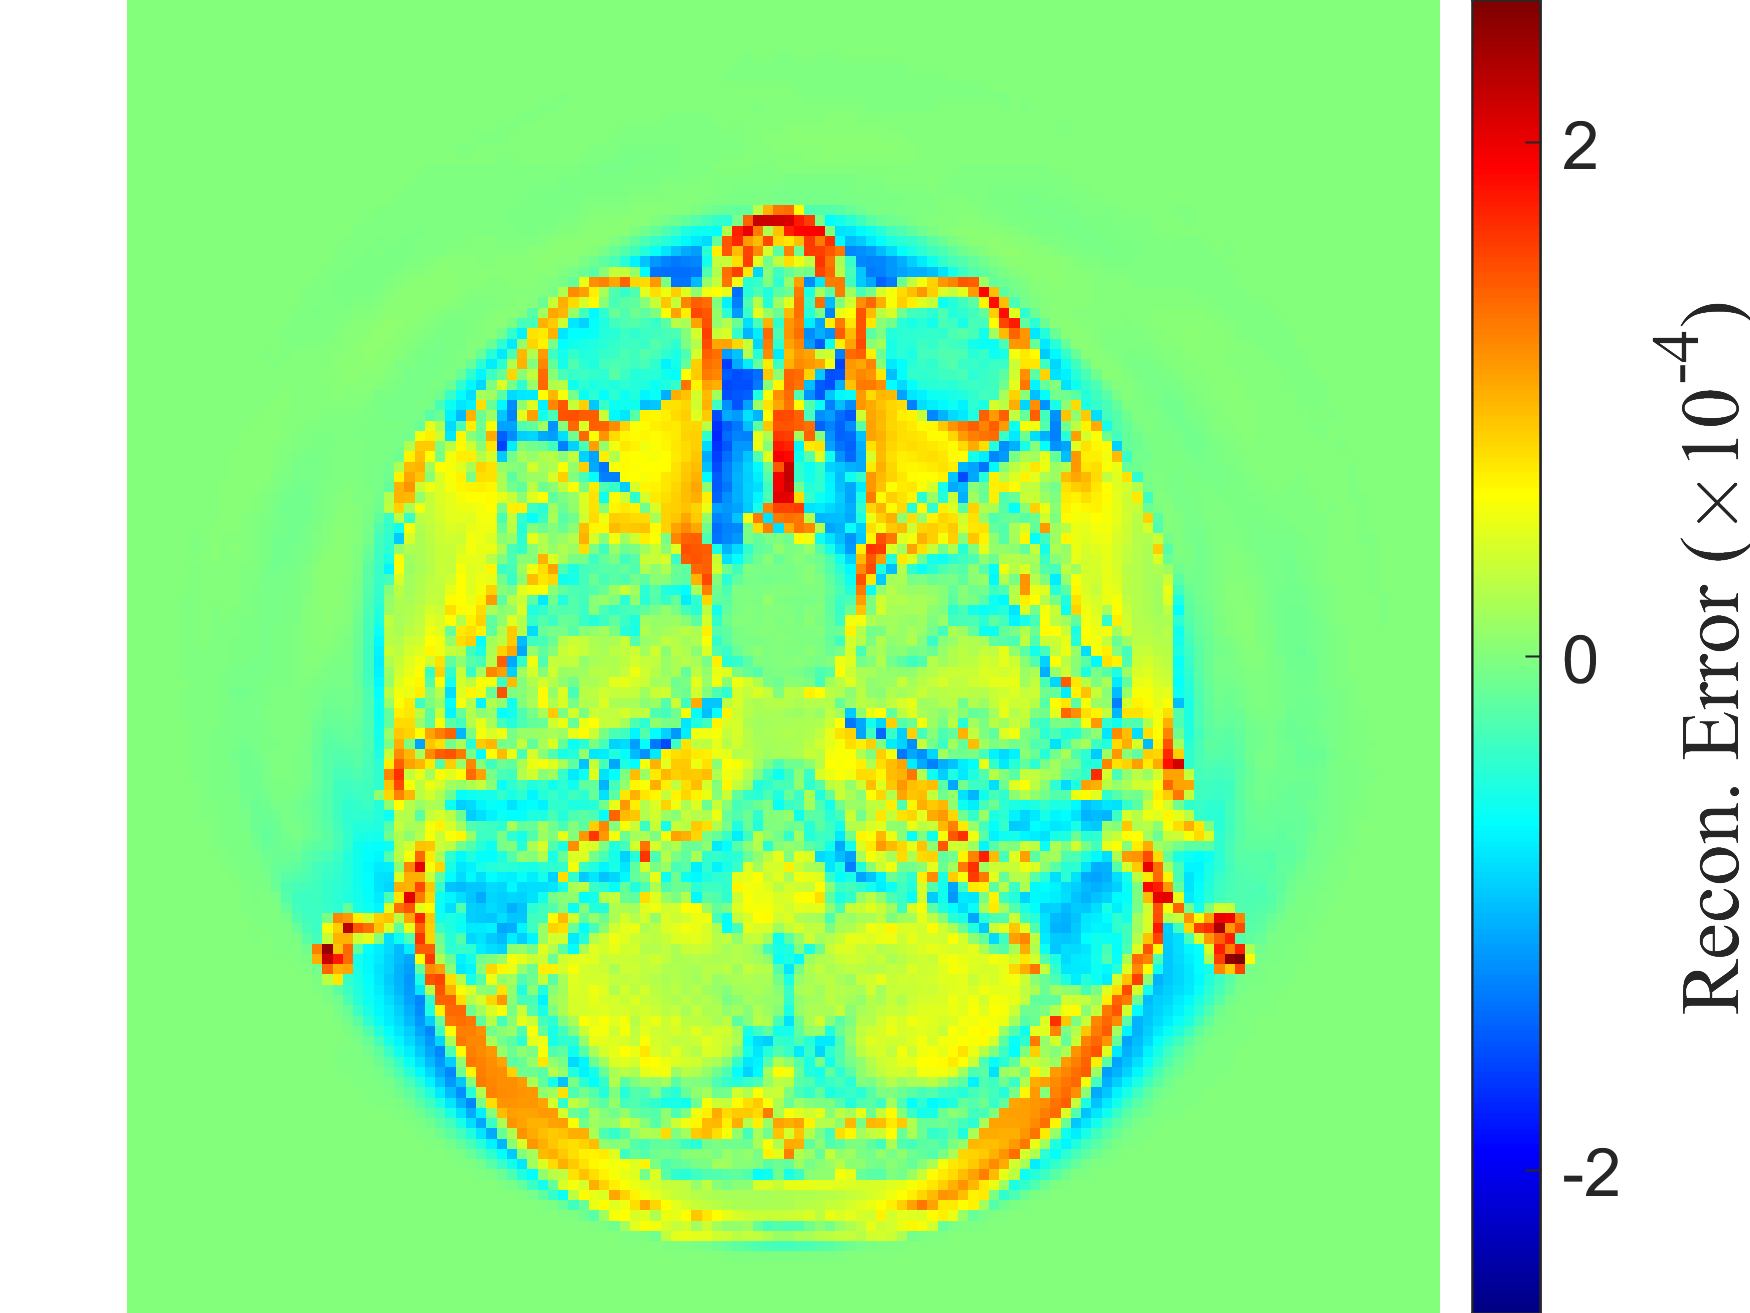

RANDSMAPs are evaluated against three mass-preserving benchmark examples with varying scalability: a moderate-dimensional 1D traffic density dataset from the Lighthill-Whitham-Richards (LWR) hyperbolic PDE; a high-dimensional 2D gray-scale MRI image dataset with sparse observations; and a high-dimensional 2D pedestrian density dataset governed by the Hughes crowd dynamics PDEs. Additionally, two classic low-dimensional manifold learning examples without inherent mass conservation (the classic 33-dimensional Swiss roll and S-curve projected in 2020 dimensions) are included to establish a baseline for RFNN decoder performance. In all examples, RANDSMAPs are compared against the DDM and kk-NN decoders. To ensure fair assessment, all decoders operate on the same low-dimensional embedding/encoding, obtained here via the DM algorithm, though each decoder is, in principle, compatible with any embedding.

Here, we evaluate the performance of the RANDSMAP decoder for pre-image reconstruction, comparing it with the standard RFNN decoder and the numerical analysis-based DDM and kk-NN decoders. The assessment focuses on three mass-preserving physical systems of increasing dimensionality and complexity (Sections 5.1-5.3). To establish a performance baseline in a general non-conservative setting, we also include two classic manifold learning examples, the Swiss roll and the S-curve projected in 2020-dimensions; results for these examples are provided in Appendices E and F.

For both the RANDSMAP (conservative) and RFNN (non-conservative) decoders, we examine three variants distinguished by their random feature mapping: random Fourier features (RFF), multi‑scale random Fourier features (MS‑RFF), and sigmoidal features (Sig). All decoders reconstruct ambient space states from low‑dimensional embeddings obtained via the DM algorithm.

For each problem, the performance of each decoder is evaluated based on (i) reconstruction accuracy, (ii) computational cost, and (iii) conservation accuracy. We quantify the reconstruction accuracy of each decoder by its relative L2L_{2} and LL_{\infty} reconstruction error across the training and testing sets, 𝒳tr\mathcal{X}_{tr} and 𝒳ts\mathcal{X}_{ts}, respectively. To assess computational cost, we recorded the computational times required for both training and inference. Training time includes encoder training (DM algorithm), hyperparameter tuning (of a single parameter for each decoder) over a held-out validation set 𝒳vl\mathcal{X}_{vl}, and decoder training. Inference time covers the complete end-to-end pipeline on the testing set 𝒳ts\mathcal{X}_{ts}, including the encoding to obtain the embedding and the decoding to reconstruct the entire testing set. To assess conservation accuracy, we quantify the pointwise deviation from the exact sum-to-one invariant in Eq. (6). As the RANDSMAP decoder is designed to preserve the sum-to-one invariant by construction, we verify this numerically and demonstrate that it maintains competitive reconstruction performance. To account for the stochasticity inherent to the random feature construction, all reported results for the RANDSMAP and RFNN decoders are averaged over 100 independent runs. The complete implementation details, including dataset generation, train/validation/test splits, feature construction sampling procedures, hyperparameter grids, and solver specifications, are provided in Appendix D.